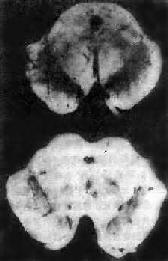

图16-35 Parkinson病 中脑黑质脱色(下),正常中脑黑质完好(上) 由于黑质细胞的变性和脱失,多巴胺合成减少,以致多巴胺(抑制性)与乙酰胆碱(兴奋性)的平衡失调而致病。近年来用左旋多巴(多巴胺的前体)来补充脑组织中多巴胺不足或用抗胆碱能药物以抑制乙酰胆碱的作用,对本病有一定的疗效。

三、震颤性麻痹震颤性麻痹(paralysis agitans)又称Parkinson病,是一种缓慢进行性疾病,多发生在50~80岁。临床表现为震颤、肌强直、运动减少、姿势及步态不稳、起步及止步困难、假面具样面容等。 本病的发生与纹状体黑质多巴胺系统损害有关,最主要的是原因不明性(特发性)Parkinson病,其他如甲型脑炎后,动脉硬化,及一氧化碳、锰、汞中毒等,均可产生类似震颤性麻痹症状或病理改变。这些情况统称为Parkinson综合征。 【病理变化】 黑质和蓝斑脱色是本病肉眼变化的特点(图16-35)。镜下可见该处的黑色素细胞丧失,残留的神经细胞中有Lewy小体形成,该小体位于胞浆内,呈圆形,中心嗜酸性着色,折光性强,边缘着色浅。电镜下,该小体由细丝构成,中心细丝包捆致密,周围则较松散。